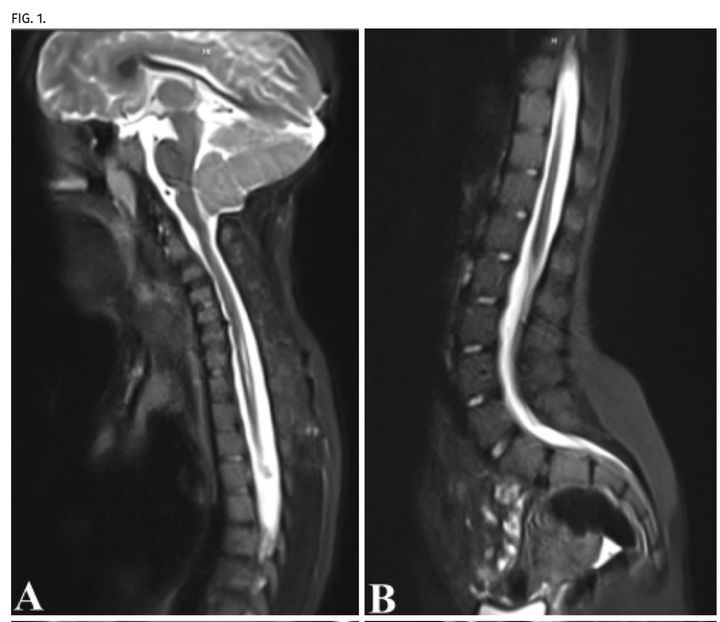

Use of fast-sequence spine MRI in pediatric patients

J Neurosurg Pediatr. 2020 Sep 18;26(6):676-681.

The immediate and long-term risk of anesthesia in the pediatric population is controversial. Traditional spine MRI protocols require the patient to remain still during the examination, and in young children this frequently results in the need for sedation administration. The authors' goal was to develop an abbreviated spine MRI protocol to reduce sedation administration in young patients undergoing spine MRI. The authors report the first pediatric series of a fast spine MRI protocol for use in young patients. The protocol does not require sedation and is able to identify and monitor syrinx, spinal dysraphism, and potentially other intraspinal anomalies.

Access full-length article here: https://pubmed.ncbi.nlm.nih.gov/32947256/